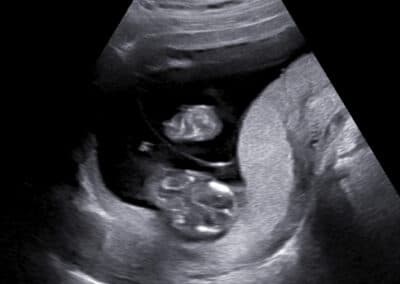

Vyšetření počtu placent, tzn. chorionicity –monochoriální biamniální dvojčetné (jednovaječné) těhotenství, které je více rizikové ohledně výskytu komplikací

Vyšetření počtu placent, tzn. chorionicity –bichoriální biamniální dvojčetné (dvoj-, ale může být, i když méně často, jedno-vaječné) těhotenství, které je méně rizikové ohledně výskytu komplikací